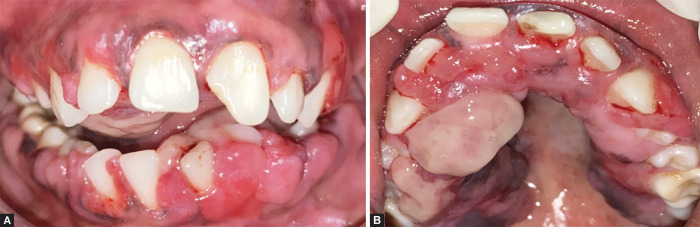

Case description: A 15-year-old girl presented with a generalized, severe, disfiguring PGE involving the entire maxillary and mandibular arch, causing an impairment of oral hygiene, mastication, speech, and esthetics. Clinical indices and oral health impact profile-14 were recorded at baseline, 1, 6, 9, 12, and 18 months. Phenytoin was replaced by the drugs levetiracetam and oxycarbamazepine. NSPT was initiated, which included plaque control measures and oral prophylaxis. There was a consistent improvement in OHRQoL scores from baseline (score 52 out of 56) to 6 months (score 15; 70% improvement) and a decrease of subscale scores (score 8-2) for psychological discomfort, psychological disability, and social disability, following drug substitution and NSPT. Thereafter, the relatively smaller, nonresponsive, persistent growth was treated with gingivectomy. Complete restoration of gingival health and no signs of recurrence were seen at 18 months (score 0).